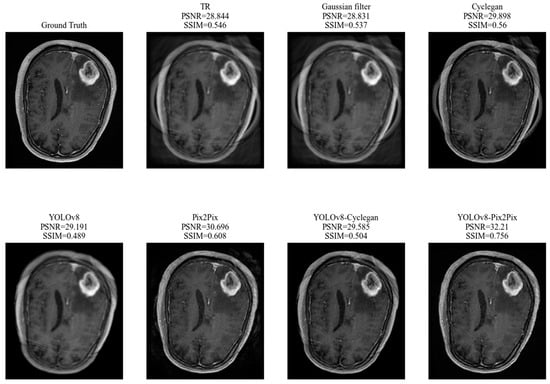

| TR | Gaussian Filter | Cyclegan | Pix2Pix | YOLOv8 | YOLOv8-Cyclegan | YOLOv8-Pix2Pix | |

|---|---|---|---|---|---|---|---|

| PSNR | 28.918 | 28.821 | 29.998 | 30.421 | 29.113 | 29.568 | 31.459 |

| SSIM | 0.566 | 0.526 | 0.571 | 0.612 | 0.491 | 0.513 | 0.650 |